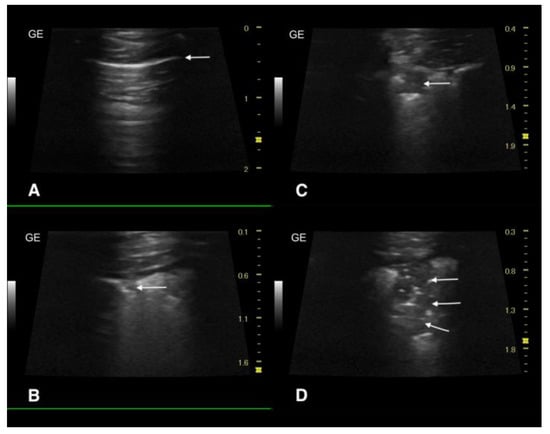

2.3. Ultrasound Examination and X-ray

3.3. Ultrasound Examination and X-ray